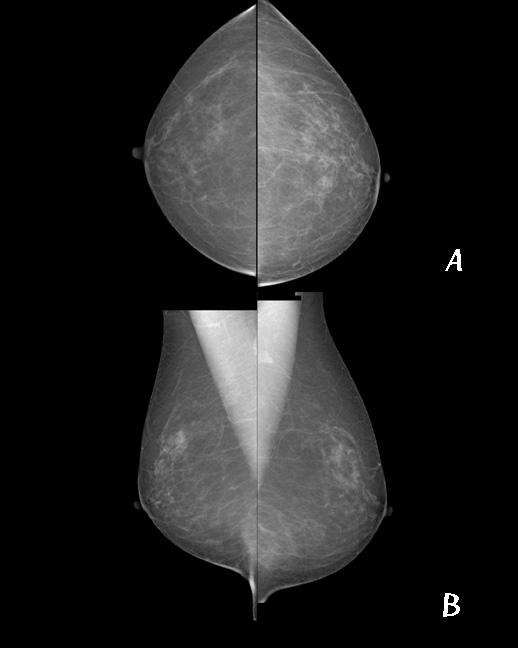

장비위에 유방을 놓고 최대한 유방이 포함되게 자세를 잡은 뒤 충분히 압박하여 검사합니다.

기본적으로는 한쪽 유방에 A : 상 하 방향(up-and down view, Cranial-caudal;CC), B : 내 외 방향(side-to-side view, medial-lateral-oblique;MLO)으로 각 2번씩 총 4번 촬영 합니다. 검사 시 압박에 의한 통증으로 인해 불편함이 있을 수 있으나 최대한 움직이지 않으셔야 움직임으로 인한 재촬영을 피할 수 있습니다.